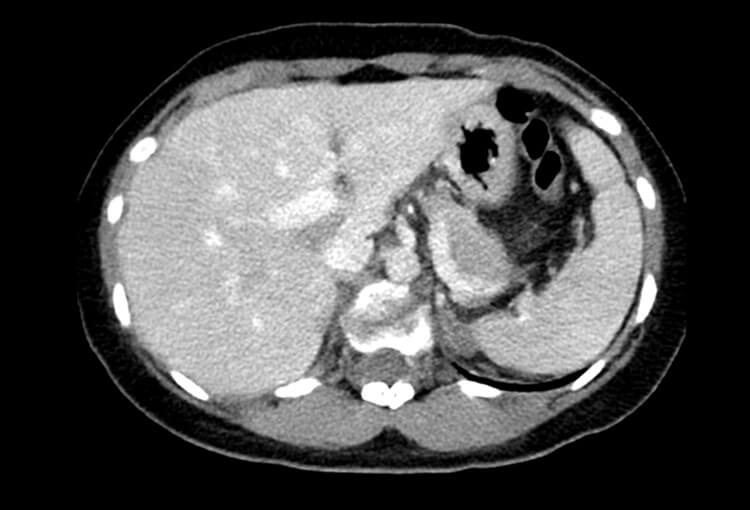

120 kV / 20 mAs / 1 mm

Before FBP (Noise 189) VS After ClariCT.AI (Noise 46) 76% Denoising